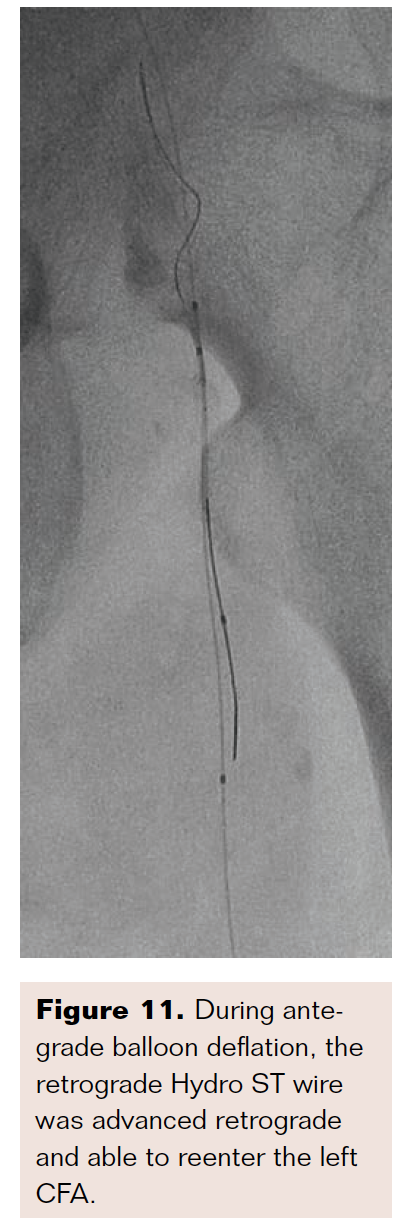

Knowing our initial retrograde left proximal SFA needle/wire access was intraluminal, we advanced a 3 mm × 40 mm balloon over the antegrade wire into the left CFA/proximal SFA junction and inflated this to nominal pressure to create a new more “reentry-ready” proximal cap (Figures 9A and 10). During antegrade balloon deflation, the retrograde Hydro ST wire was advanced and able to reenter the left CFA (Figures 9B and 11). This wire was inserted into the antegrade sheath (Figure 9C). Through microcatheter exchange, we advanced a Grand Slam wire (Asahi Intecc) antegrade with the tip left in the left popliteal artery rather than the PT to avoid being occlusive at the single runoff vessel. It also allowed us to reduce the risk of causing slow flow and “trashed foot” during intervention, including during atherectomy.